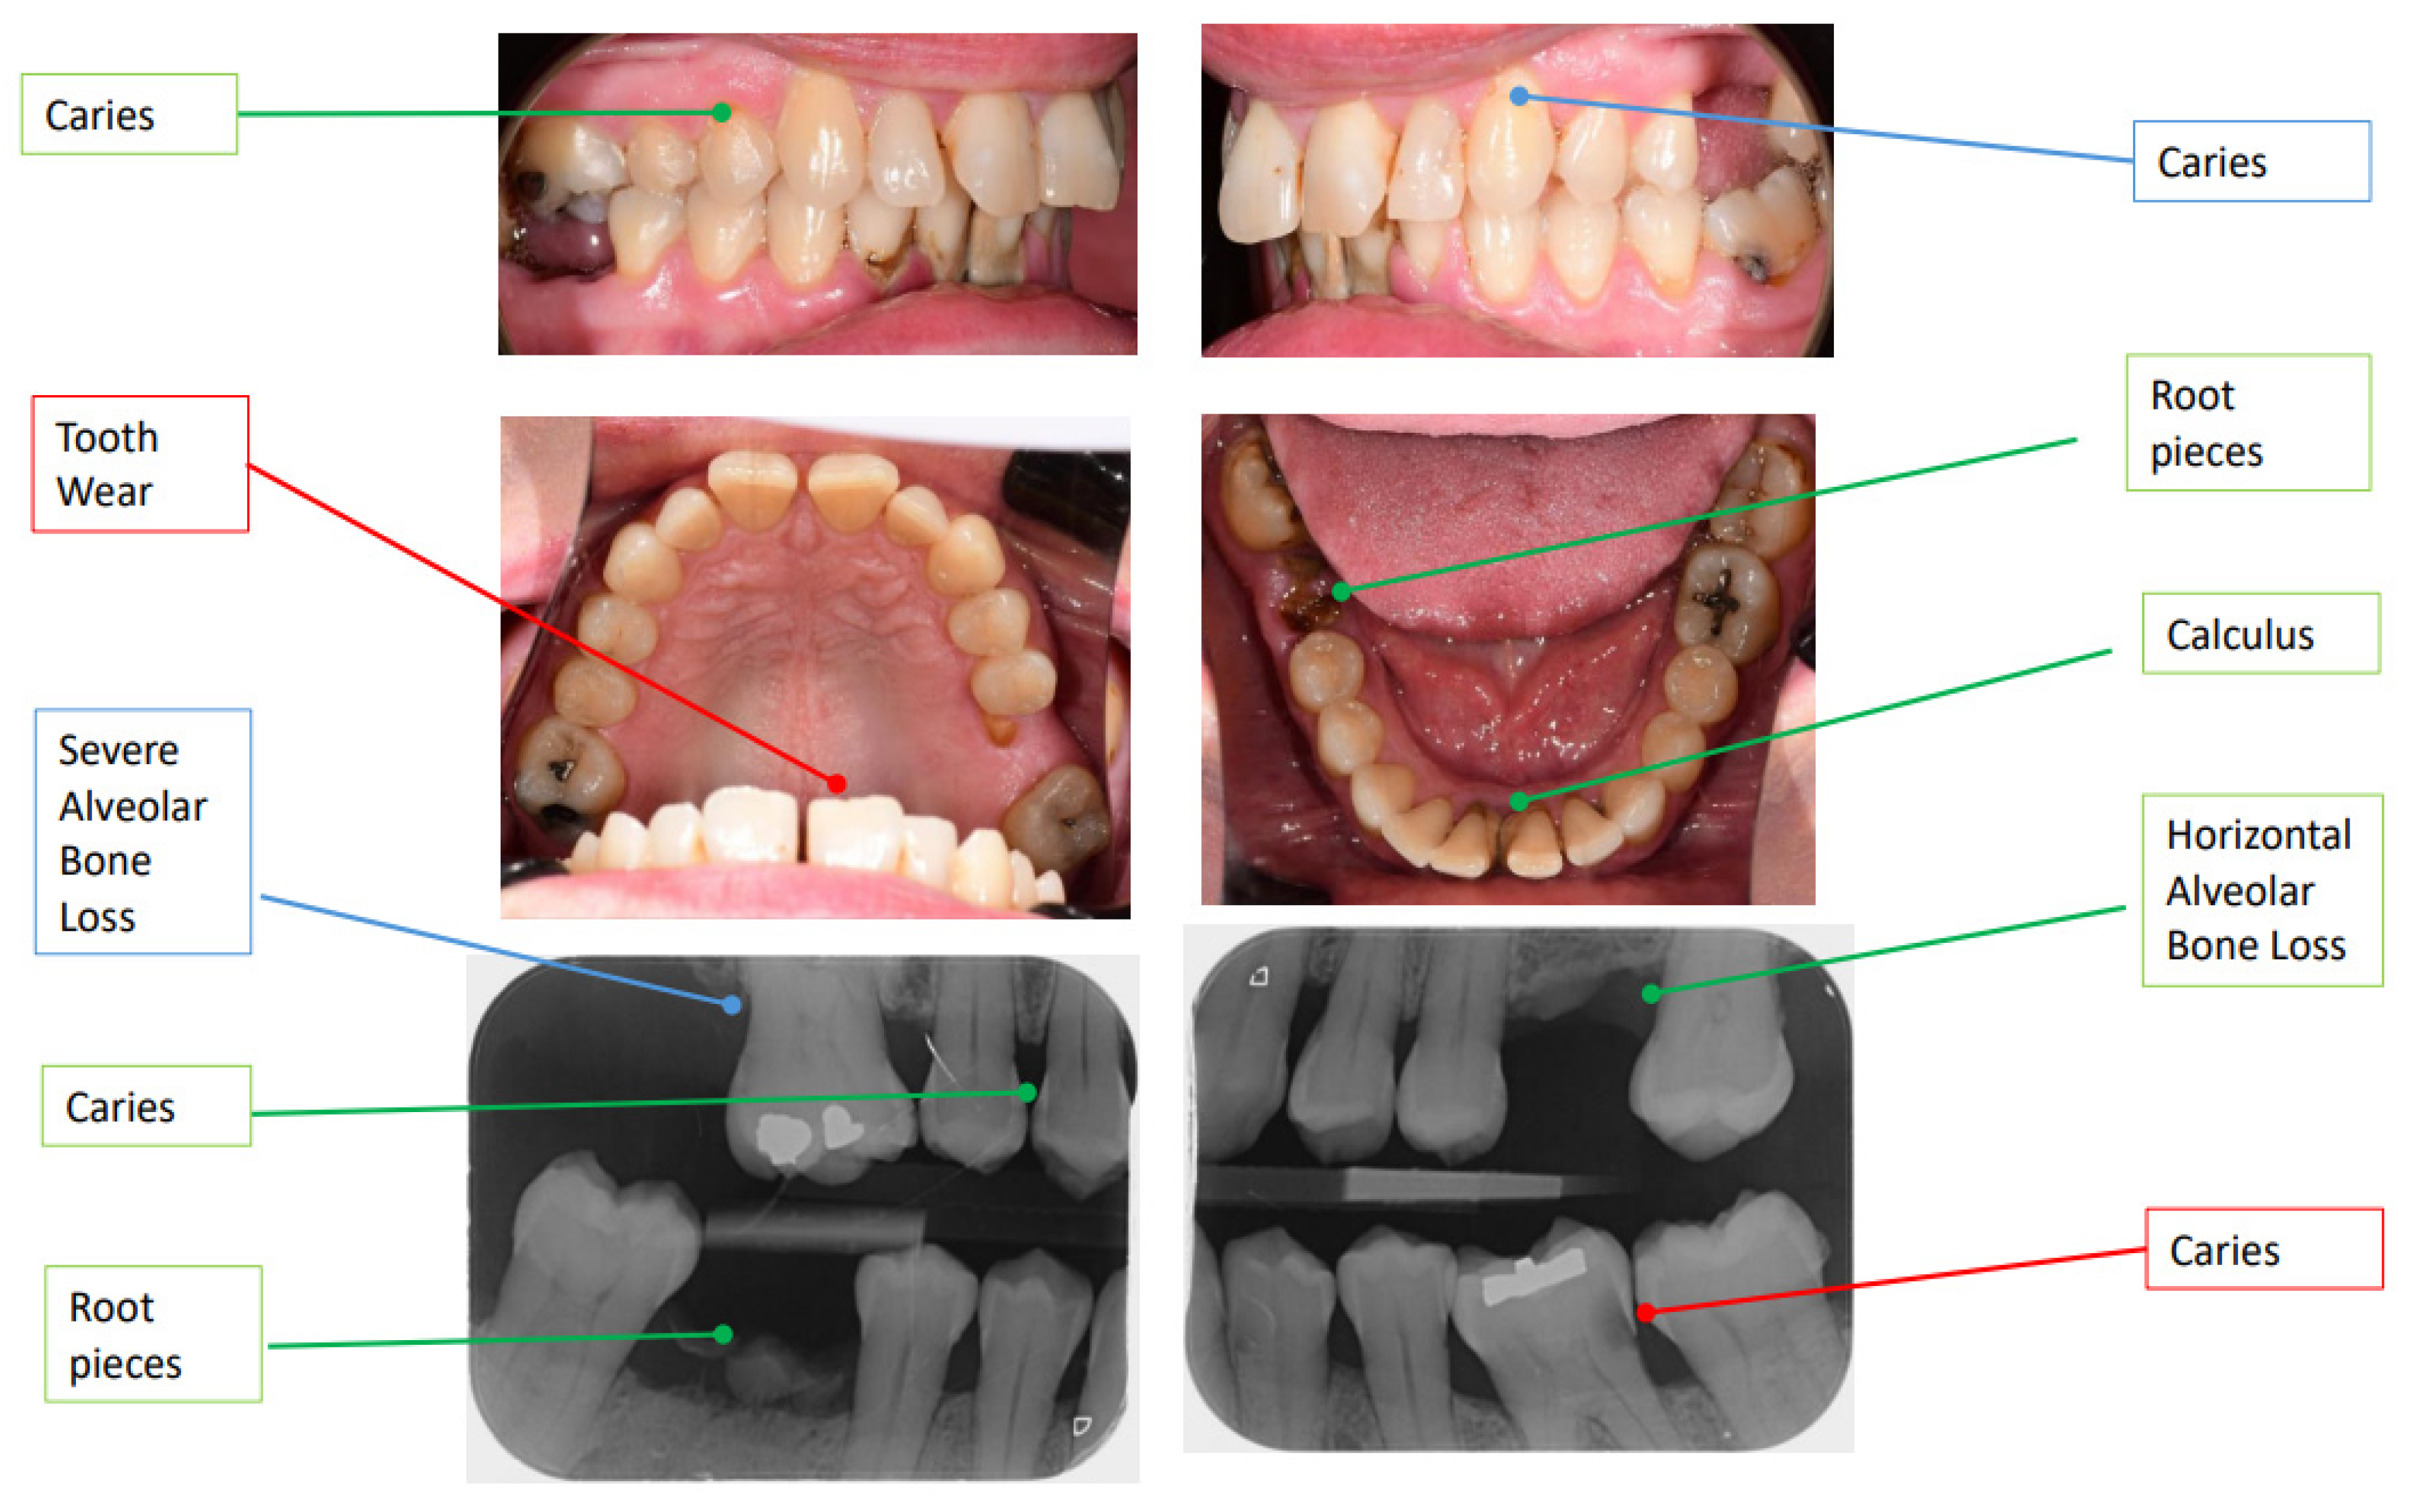

5. Case Study: AI-Powered Dental Caries Detection and Management

| Tooth, Surface | Detection Mode | Findings/OD | Treatment Plan (Procedure) | Item Code | Cost | Inference | |

|---|---|---|---|---|---|---|---|

| Dentist | 23 | Inspection | Initial caries | Adhesive restoration—anterior tooth—direct | 522 | $228.99 | Dentist false positive |

| 14 | Inspection | Moderate caries | Adhesive restoration—posterior tooth—direct | 533 | $286.01 | Dentist true positive | |

| CoTreat Navigator® | 36D 4 | PBW 1 | Initial Stage ICCMS RA 3 2 | Adhesive restoration—posterior tooth—direct | 532–535 | $244.53–$383.93 | Dentist false negative |

| 36B | Photo | Moderate caries ICDAS Code 3 3 | |||||

| 14DM | PBW 1 | Initial Stage ICCMS RA 3 2 | Adhesive restoration—posterior tooth—direct | 533–535 | $286.01–$383.93 | Dentist true positive | |

| 14B | Photo | Moderate caries ICDAS Code 3 3 |